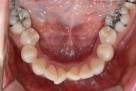

치료 전

치료 후

[덧니_비발치]

잔체교정 (30대 여성)